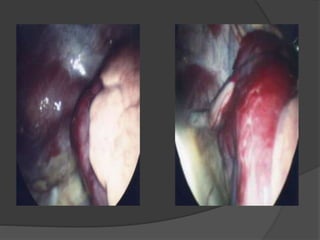

 +++ thoracoscopie; thoracotomie vidéo-

assistée

 Voies d’abords:

 Thoracotomie +/- vidéo-assistée

 Thoracoscopie exclusive

Prise en chargeet traitement (2)  Comment ?  CHIRURGIE +++ / Réanimation péri-opératoire  Territoire difficile à repérer : exérèse complète  Voies d’abords:  Thoracotomie +/- vidéo-assistée  Thoracoscopie exclusive  Thoracotomie de décompression  Lobectomie/ bi-lobectomie/ traitement étiologique

• #113 Vue vidéothoracoscopique G -Poumon séquestré -Poumon normal